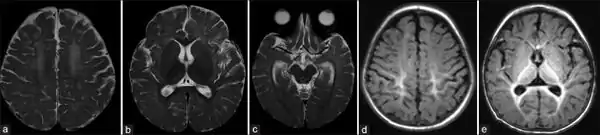

Figures